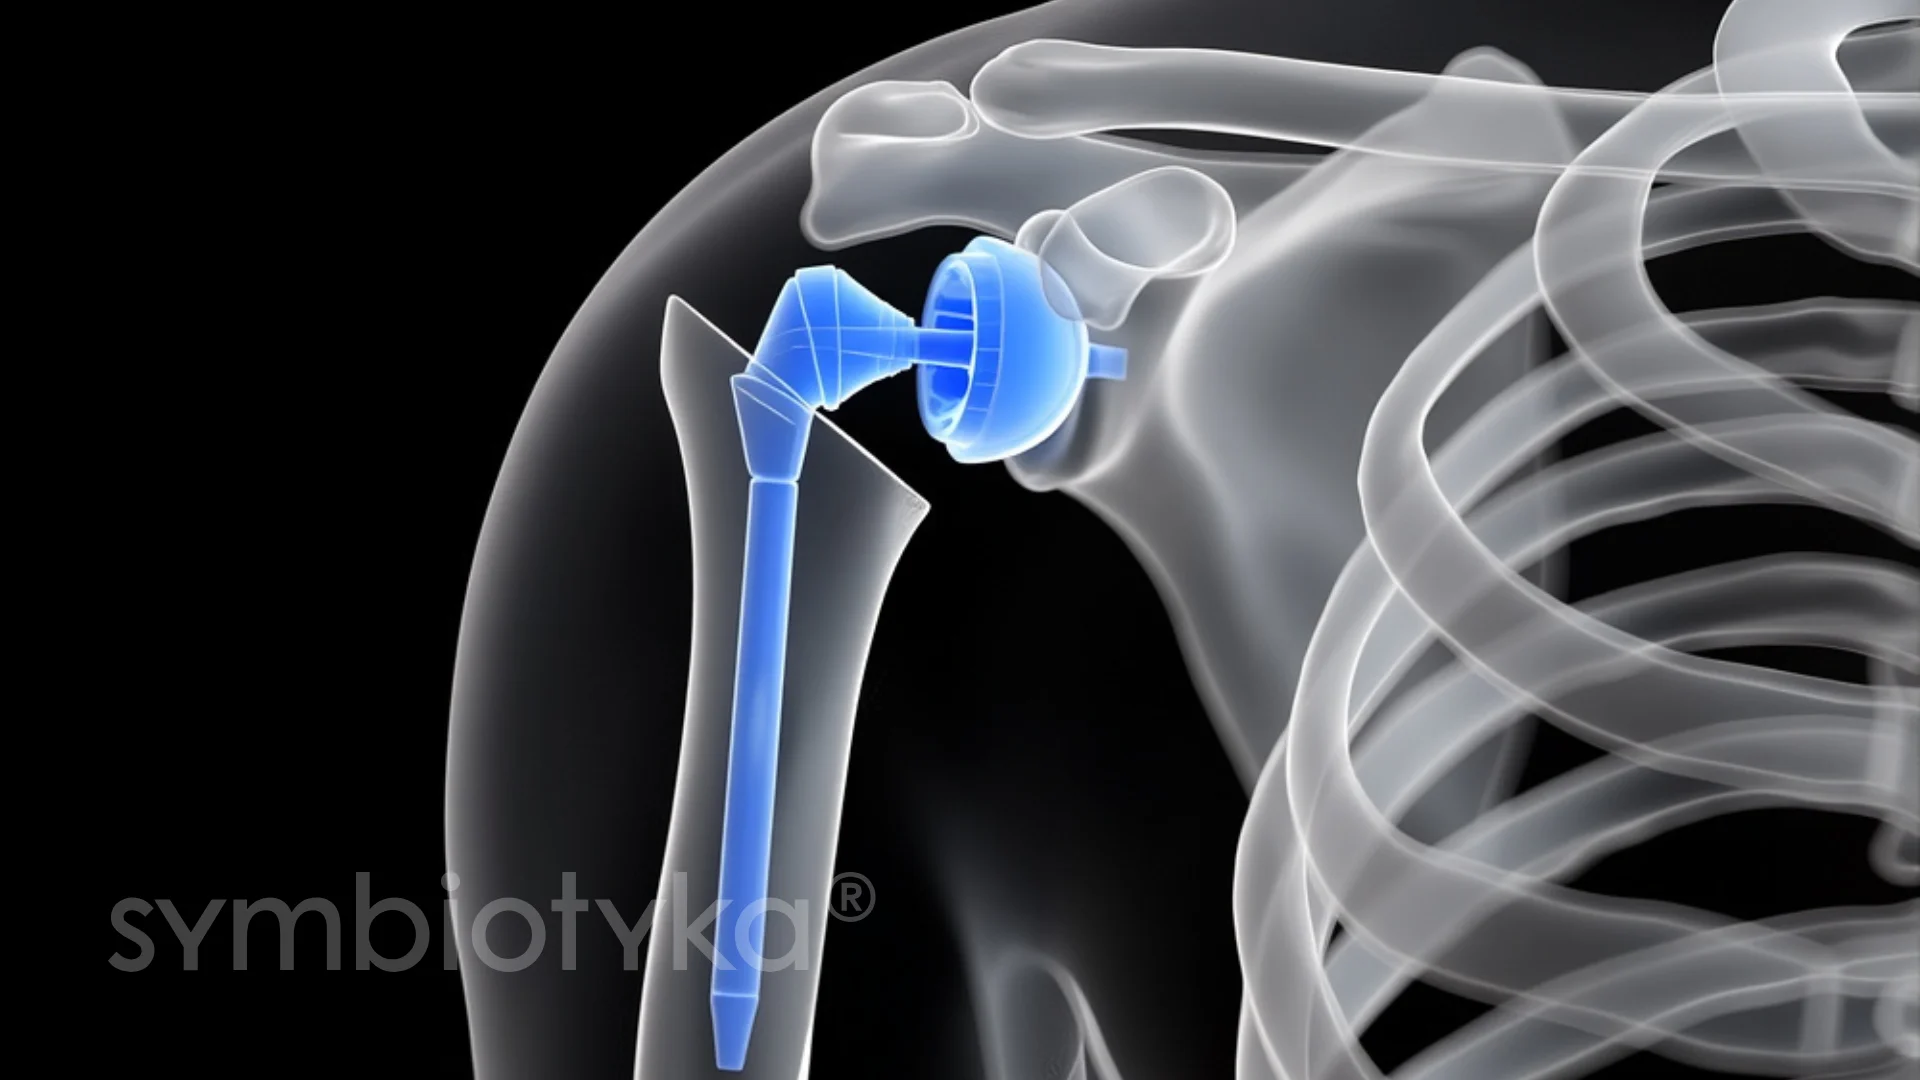

Ендопротезування плечового суглоба — це високотехнологічна ортопедична операція, під час якої пошкоджені або зношені частини плеча замінюють на штучні імпланти. Таке втручання дозволяє усунути біль, відновити обсяг рухів у руці та повернути пацієнтові можливість жити повноцінним активним життям.

Ендопротезування вирішує цю проблему завдяки заміні пошкоджених елементів на спеціально розроблені імпланти з металу, кераміки або полімерних матеріалів.

У плечовій кістці формується канал для встановлення ніжки імпланта. Поверхня западини лопатки обробляється для точного розташування штучної «чаші».

Хірург перевіряє плавність рухів та надійність фіксації протеза, щоб уникнути розхитування або обмеження амплітуди.